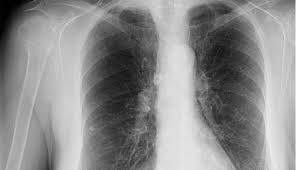

Lung Cancer Symptoms Signs Stages And More from post.medicalnewstoday.com Cigarette smoking is the most important cause of lung cancer. Around 8 in 10 cases develop in people over the age of 60. Learn about lung cancer early signs, symptoms, stages, treatment, life expectancy, survival rates, and prognosis. Tobacco smoke contains many chemicals that are known to cause lung cancer. Lung cancer has almost 20 types and can affect both genders. What are the symptoms of lung cancer? You may think it's irrelevant, but chronic shoulder pain can sometimes be the result of a tumor that is pressuring the nerves in the armpit, leading to tingling sensations, aches, and shooting. When lung cancer does cause signs in its early stages, they may vary from person to person but commonly include neurological changes:

Treatments are available to decrease signs and symptoms and to help you live longer. When lung cancer does cause signs in its early stages, they may vary from person to person but commonly include neurological changes: If you still smoke, quitting smoking is the single best thing you can do for your. What are the symptoms of lung cancer? However, if you're aware of even the most subtle signs of lung cancer, seek medical help when you first notice symptoms—and make sure you get screened if you're at higher risk—you have a significantly better shot of getting your lung cancer diagnosed at an earlier. Once lung cancer has spread beyond the lungs, it's generally not curable. Lung cancer occurs when cells in the lung mutate or change. Hanson explains some of the signs and symptoms of lung cancer, which include changes in cough, blood in sputum, weight change, or voice change. Cancer cancer is the second most common cause of death cancer has become more common during the 20th century, not because of pollution several human viruses have been shown to cause cancer. If any animal or human being is suspected to be suffering from plague, that animal or person should be separated from the others until the treatment is completed. The main symptoms of lung cancer include Even being near those who smoke can be dangerous. Lung cancer usually has no symptoms in its early stages.

Care guide for lung cancer. Symptoms of lung cancer develop as the condition progresses and there are usually no signs or symptoms in the early stages. The main symptoms of lung cancer include Lung cancer is the deadliest type of cancer, causing more than 150,000 deaths annually in the united states. Cancer cancer is the second most common cause of death cancer has become more common during the 20th century, not because of pollution several human viruses have been shown to cause cancer. See pictures of lung cancer. Lung cancer check up _affect humans and lung cancer is a prominent one. Possible causes, signs and symptoms, standard treatment options and means of care and support. Usually, wheezing occurs when the airways in the lungs become blocked or inflamed. Of course, if you are. You may think it's irrelevant, but chronic shoulder pain can sometimes be the result of a tumor that is pressuring the nerves in the armpit, leading to tingling sensations, aches, and shooting. Learn about lung cancer early warning signs, symptoms and treatments. There are several signs of lung cancer that are relatively common, although they can be subtle and easily attributed to something else.